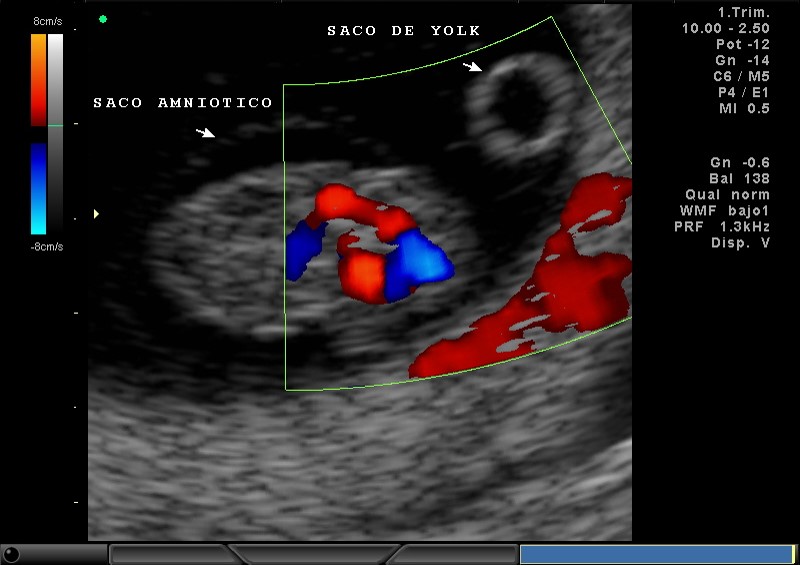

2D Y COLOR SACO AMNIOTICO, SACO DE YOLK